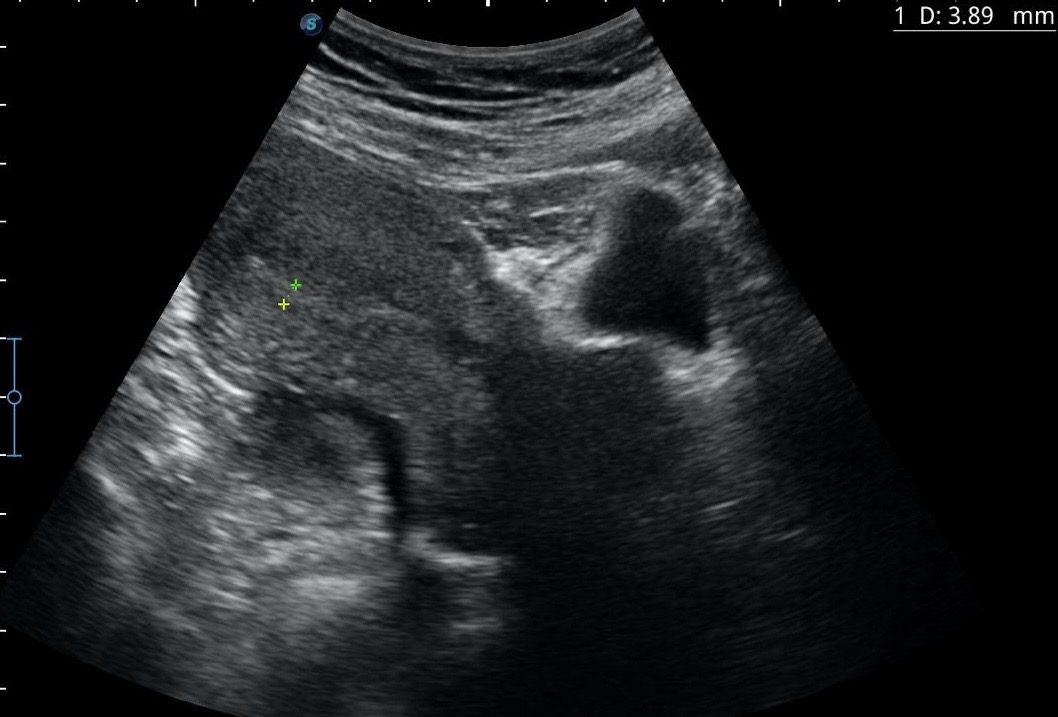

Hallazgos ecográficos abdominales: útero en anteversión, de tamaño y ecogenicidad normales; línea endometrial de 3,89 mm. No se objetiva estructura embrionaria (ni saco vitelino ni polo fetal). En anejo izquierdo se visualiza una lesión anecoica de 59,64 mm de diámetro que parece depender del mismo, no septada. No se observa líquido libre.

Lesión paranexial que podría corresponderse con un quiste simple descubierto de forma incidental. Sin visualización de saco gestacional. En urgencias hospitalarias no hubo concordancia y se diagnostica gestación incipiente.